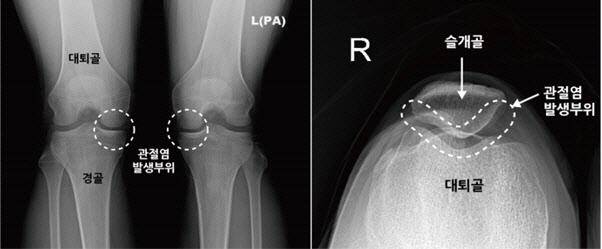

무릎 관절은 우리 몸에서 가장 큰 관절이며 슬개골(무릎뼈), 대퇴골(허벅지뼈), 경골(정강이뼈) 등 3개의 뼈로 구성돼 있다.

슬개골은 무릎을 움직일 때 지렛대 역할을 하는데, 무릎 앞에 있는 슬개골과 뒤에 있는 대퇴골 사이가 자극되면서 통증이 생기는 증상이 슬개대퇴관절염이다.

슬개대퇴관절염은 슬개골(무릎 앞 삼각형 뼈)과 대퇴골 사이에 있는 연골이 손상되거나 슬개골이 선천적으로 대퇴골에 제대로 맞지 않아 무릎을 움직일 때 슬개골이 어긋나면서 발생한다.

일반적인 퇴행성 무릎관절염은 대퇴골과 경골 사이에 있는 연골 손상 때문에 발생한다. 무릎관절염이 악화할수록 무릎 관절 간격이 좁아지므로 X선 촬영만으로 쉽게 진단할 수 있다.

하지만 슬개대퇴관절염은 어느 정도 질환이 진행돼도 X선 촬영으로는 이상 소견을 발견하기 어려워 진단이 쉽지 않다. 그래서 종종 진단과 치료 시기를 놓치게 되어 증상이 악화되기도 한다.